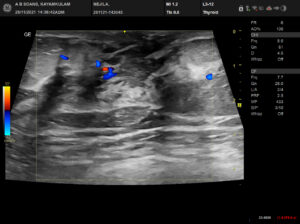

Complaints: H/o right breast pain

Case study: Well circumscribed irregular hypoechoic fluid collection measuring ~3.7 x 1.8 cm with complex mixed echogenicity showing peripheral vascularity and surrounding echogenic fat noted in the right upper midline at 12 o’clock position extending into the subareolar region.

Images:

Conclusion: Well circumscribed irregular hypoechoic complex collection in the right breast extending into the subareolar region with surrounding inflammatory changes (BIRADS category 2). – Features in favour of acute mastitis with abscess formation.